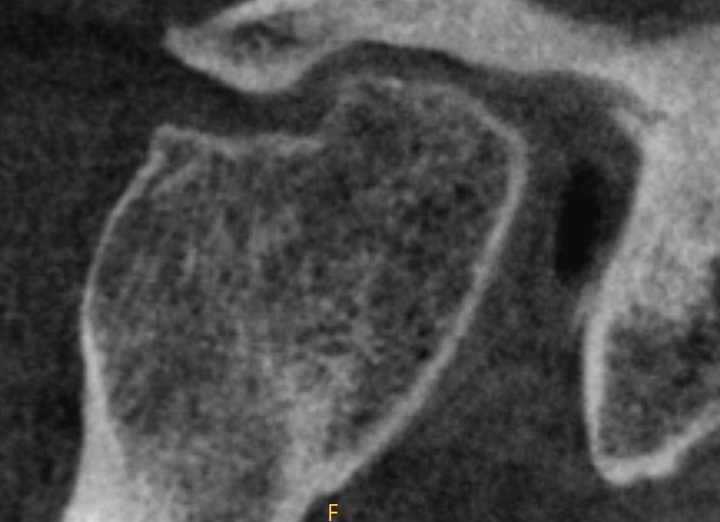

TMJ joint spaces and condylar bone: Due to the small size and complex morphology of the temporomandibular joint.

The temporomandibular joint (TMJ) is a complex, small joint where your jaw connects to your skull. Problems here can be subtle and detailed. CBCT is widely used for TMJ imaging, offering 3D views with far less radiation than traditional CT.

However, the main challenge is that the bony parts of the joint — like the condylar head and the thin bone of the glenoid fossa — often have fine features smaller than a typical CBCT voxel.

- Small holes or bone erosions may be hidden or smoothed out, making early disease hard to spot.

- Joint surfaces can look thicker, rounder, or flatter than they really are.

- Measurements of bone thickness or joint space may be inaccurate.

This is especially important for TMJ problems because many joint conditions begin with tiny changes in bone that are difficult to see unless the scan has very small voxels.